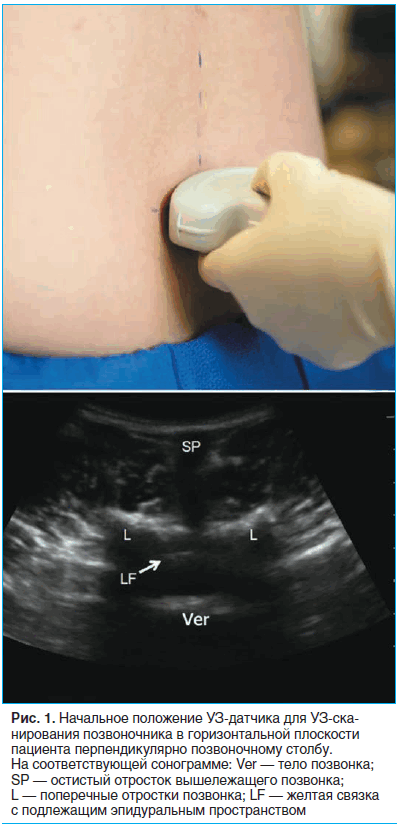

В качестве стартовой точки мы пальпаторно идентифицировали крестцовую кость и располагали датчик над ней в поперечной плоскости (рис. 1).

При этом на экране отображалась зубчатая структура кости с подлежащей акустической тенью. Затем, постепенно смещая датчик в краниальном направлении, мы отмечали остистые отростки L5, L4 и L3 позвонков. При УЗИ остистые отростки позвонков выглядят как небольшие острые с яркими гиперэхогенными краями образования, расположенные непосредственно под кожей. Обычно отросток L5 расположен несколько глубже, чем L4, но не всегда по средней линии у пациентов с выраженными скелетными деформациями. В любом случае мы отмечали медицинским маркером положение каждого остистого позвонка.